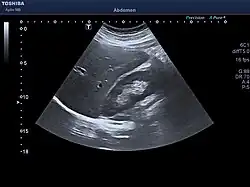

The diagnosis of liver disease is made by liver function tests, groups of blood tests, that can readily show the extent of liver damage. If infection is suspected, then other serological tests will be carried out. A physical examination of the liver can only reveal its size and any tenderness, and some form of imaging such as an ultrasound or CT scan may also be needed.

Sometimes a liver biopsy will be necessary, and a tissue sample is taken through a needle inserted into the skin just below the rib cage. This procedure may be helped by a sonographer providing ultrasound guidance to an interventional radiologist.[73]